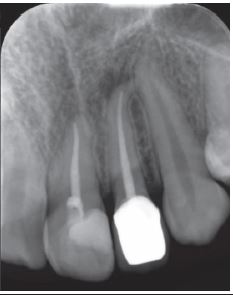

Luego se practicó endodoncia en diente 2.2 y diente 2.1 (incisivo central izquierdo); se realizó prótesis fija unitaria en diente 2.2 y se controló radiográficamente a un mes de finalizado el tratamiento endodóncico apreciándose una disminución de la zona radiolúcida (Figura 5).

Al sexto mes posterior al tratamiento, paciente refiere no tener molestia alguna. Se decide controlar con radiografía periapical de diente 2.2, con la que se verifica una disminución notable del área radiolúcida (Figura 6).